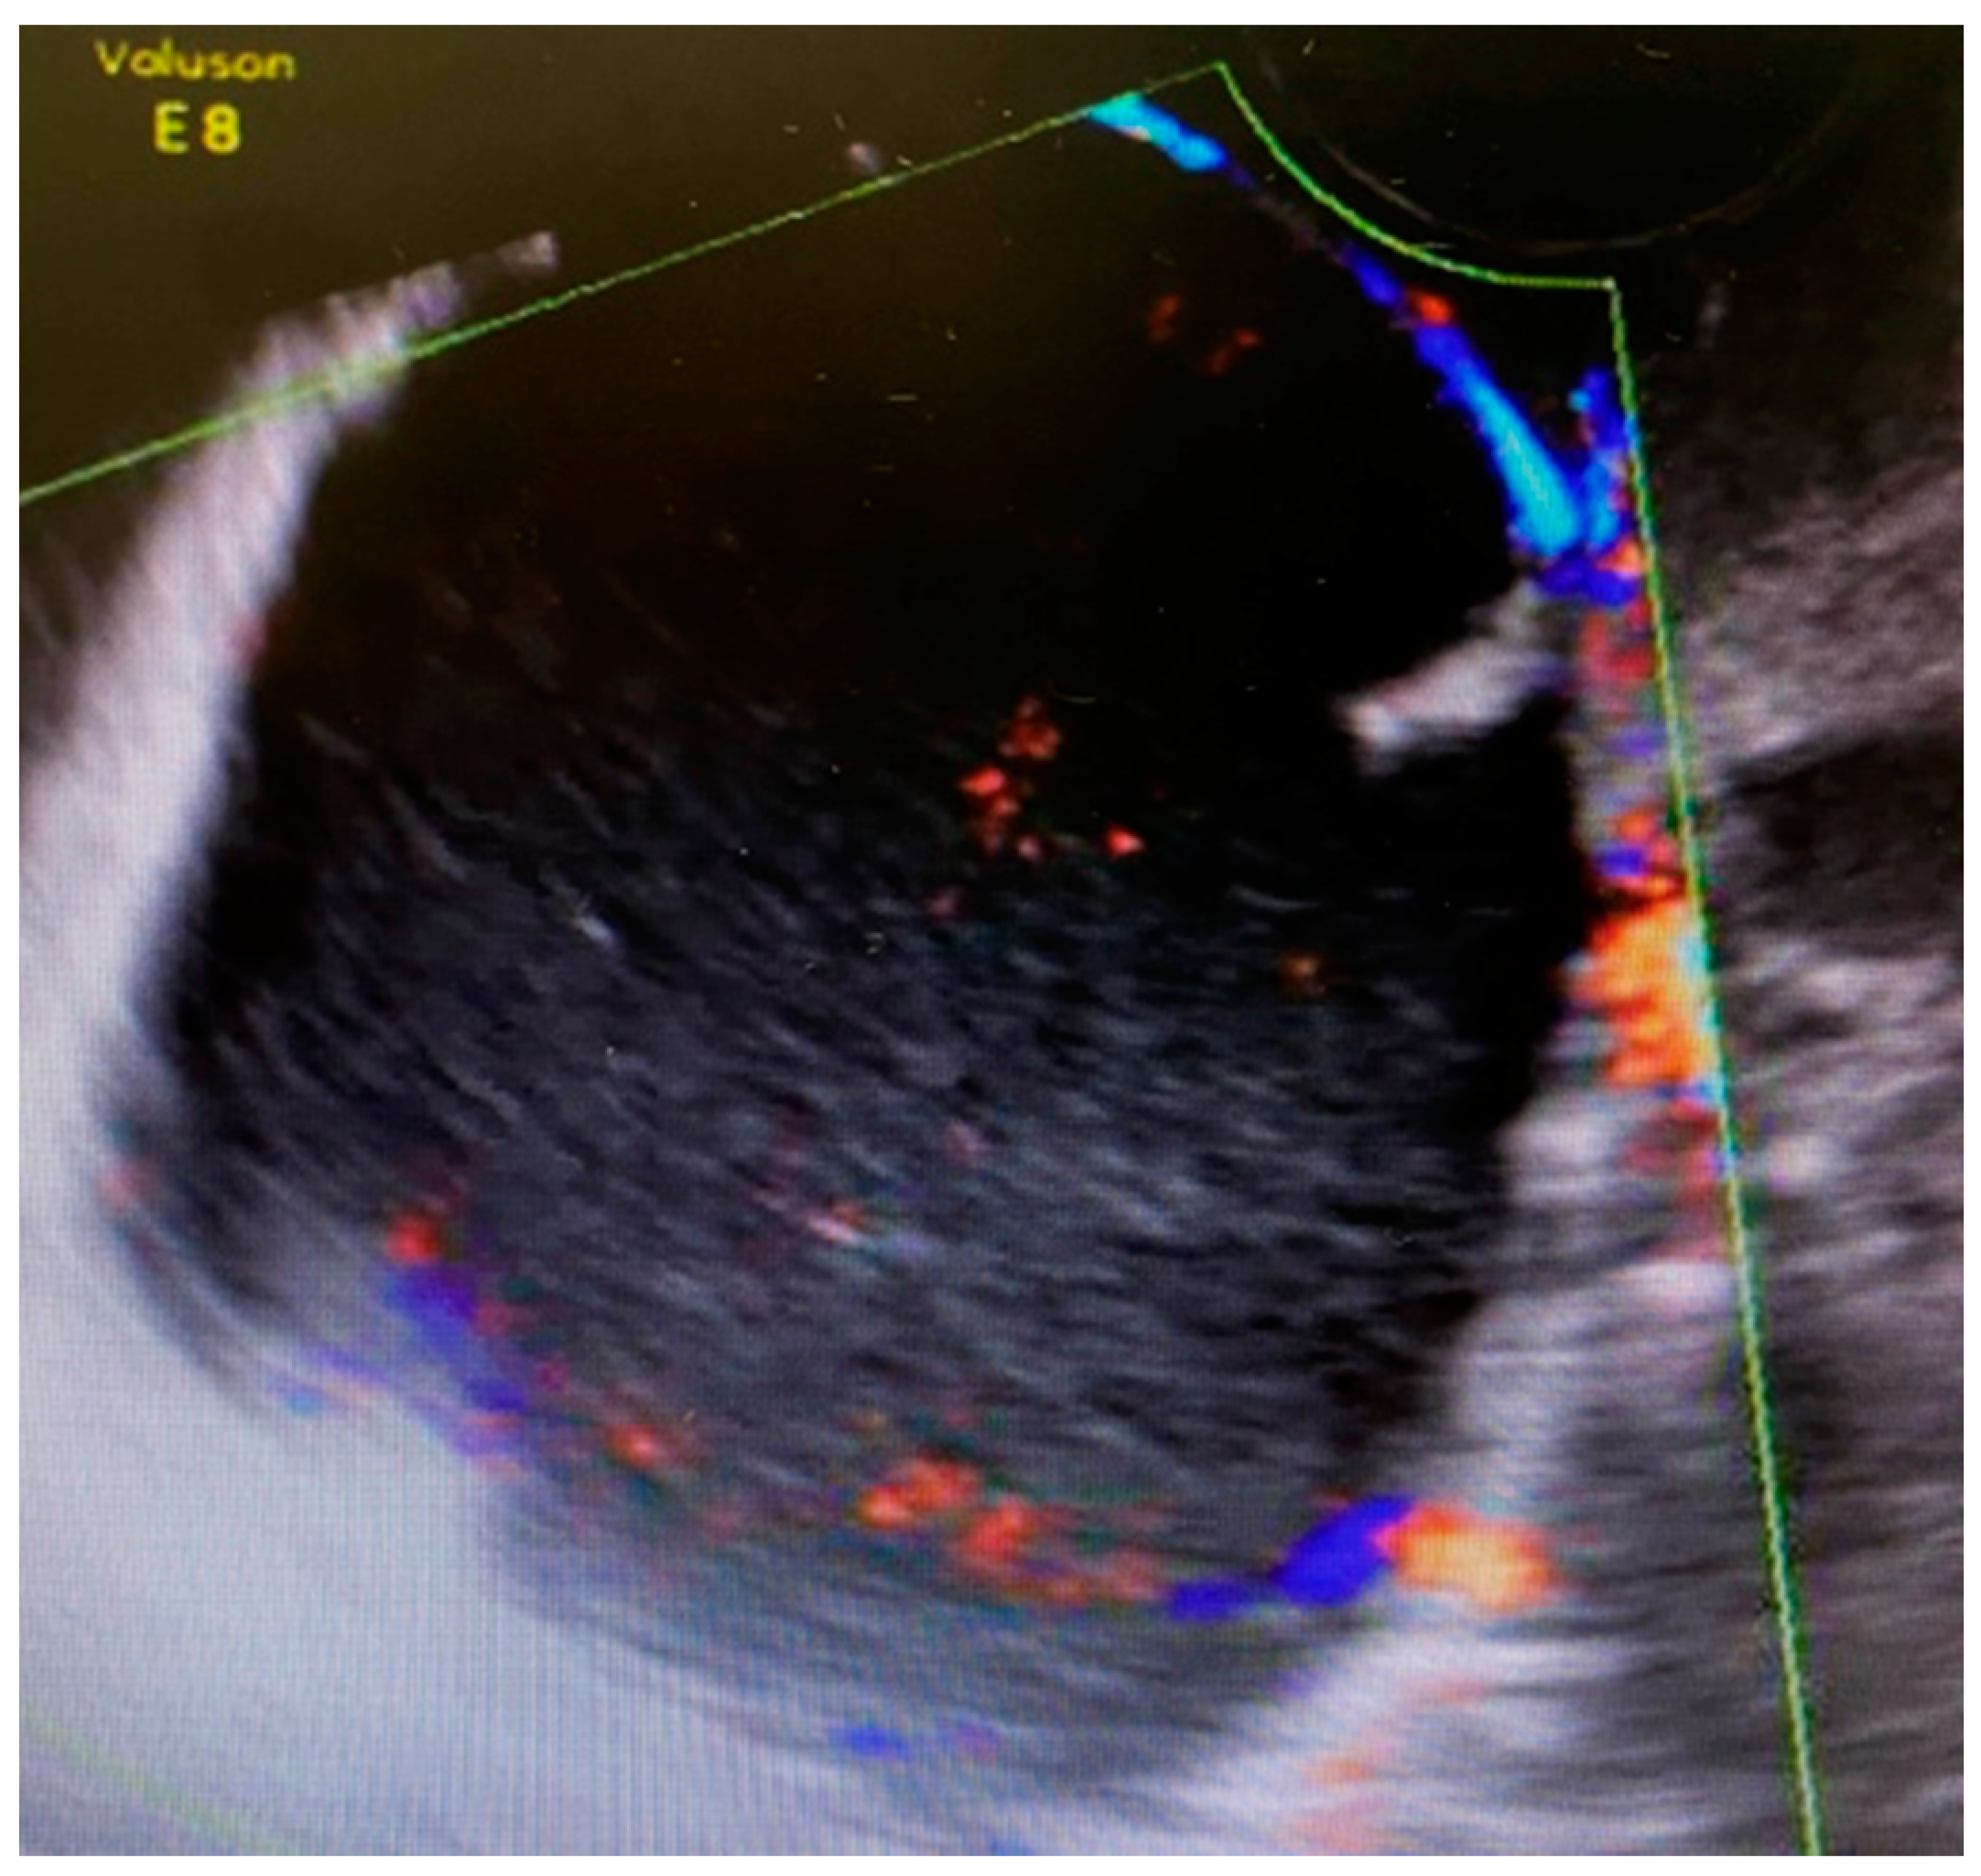

The first 12-week ultrasound showed 66 mm × 48 mm cysts between the bladder and the cervix with peripheral vascularization, and another left paracervical cystic and heterogeneous lesion of 39 mm × 26 mm size (Figure 1). A follow-up visit was indicated requiring close monitoring.

Figure 1.

Ultrasound scan compatible with complex cystic formation.